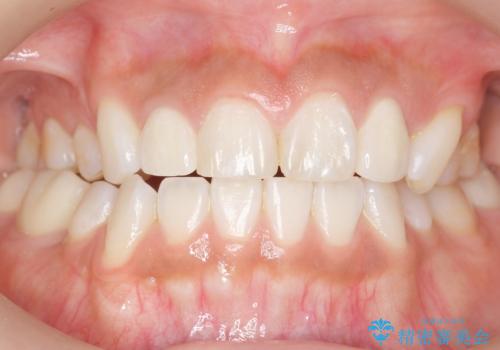

う蝕を丁寧に除去したのち、セラミックインレーによる修復を行いました。

セラミックインレーの審美的な仕上がりと自然な咬み心地にご満足頂けました。

「フロスを通したときの嫌な臭いもなくなった」と喜んで下さいました。

インレーの種類:セラミックインレー(e-max press)